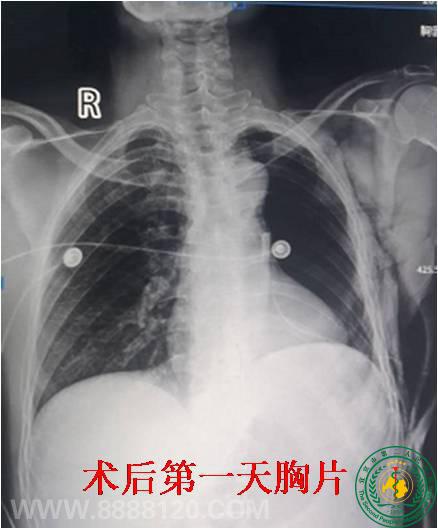

川中南首例全胸腔镜左全肺切除术在宜宾市二医院成功完成

川中南首例全胸腔镜左全肺切除术在宜宾市二医院成功完成18926